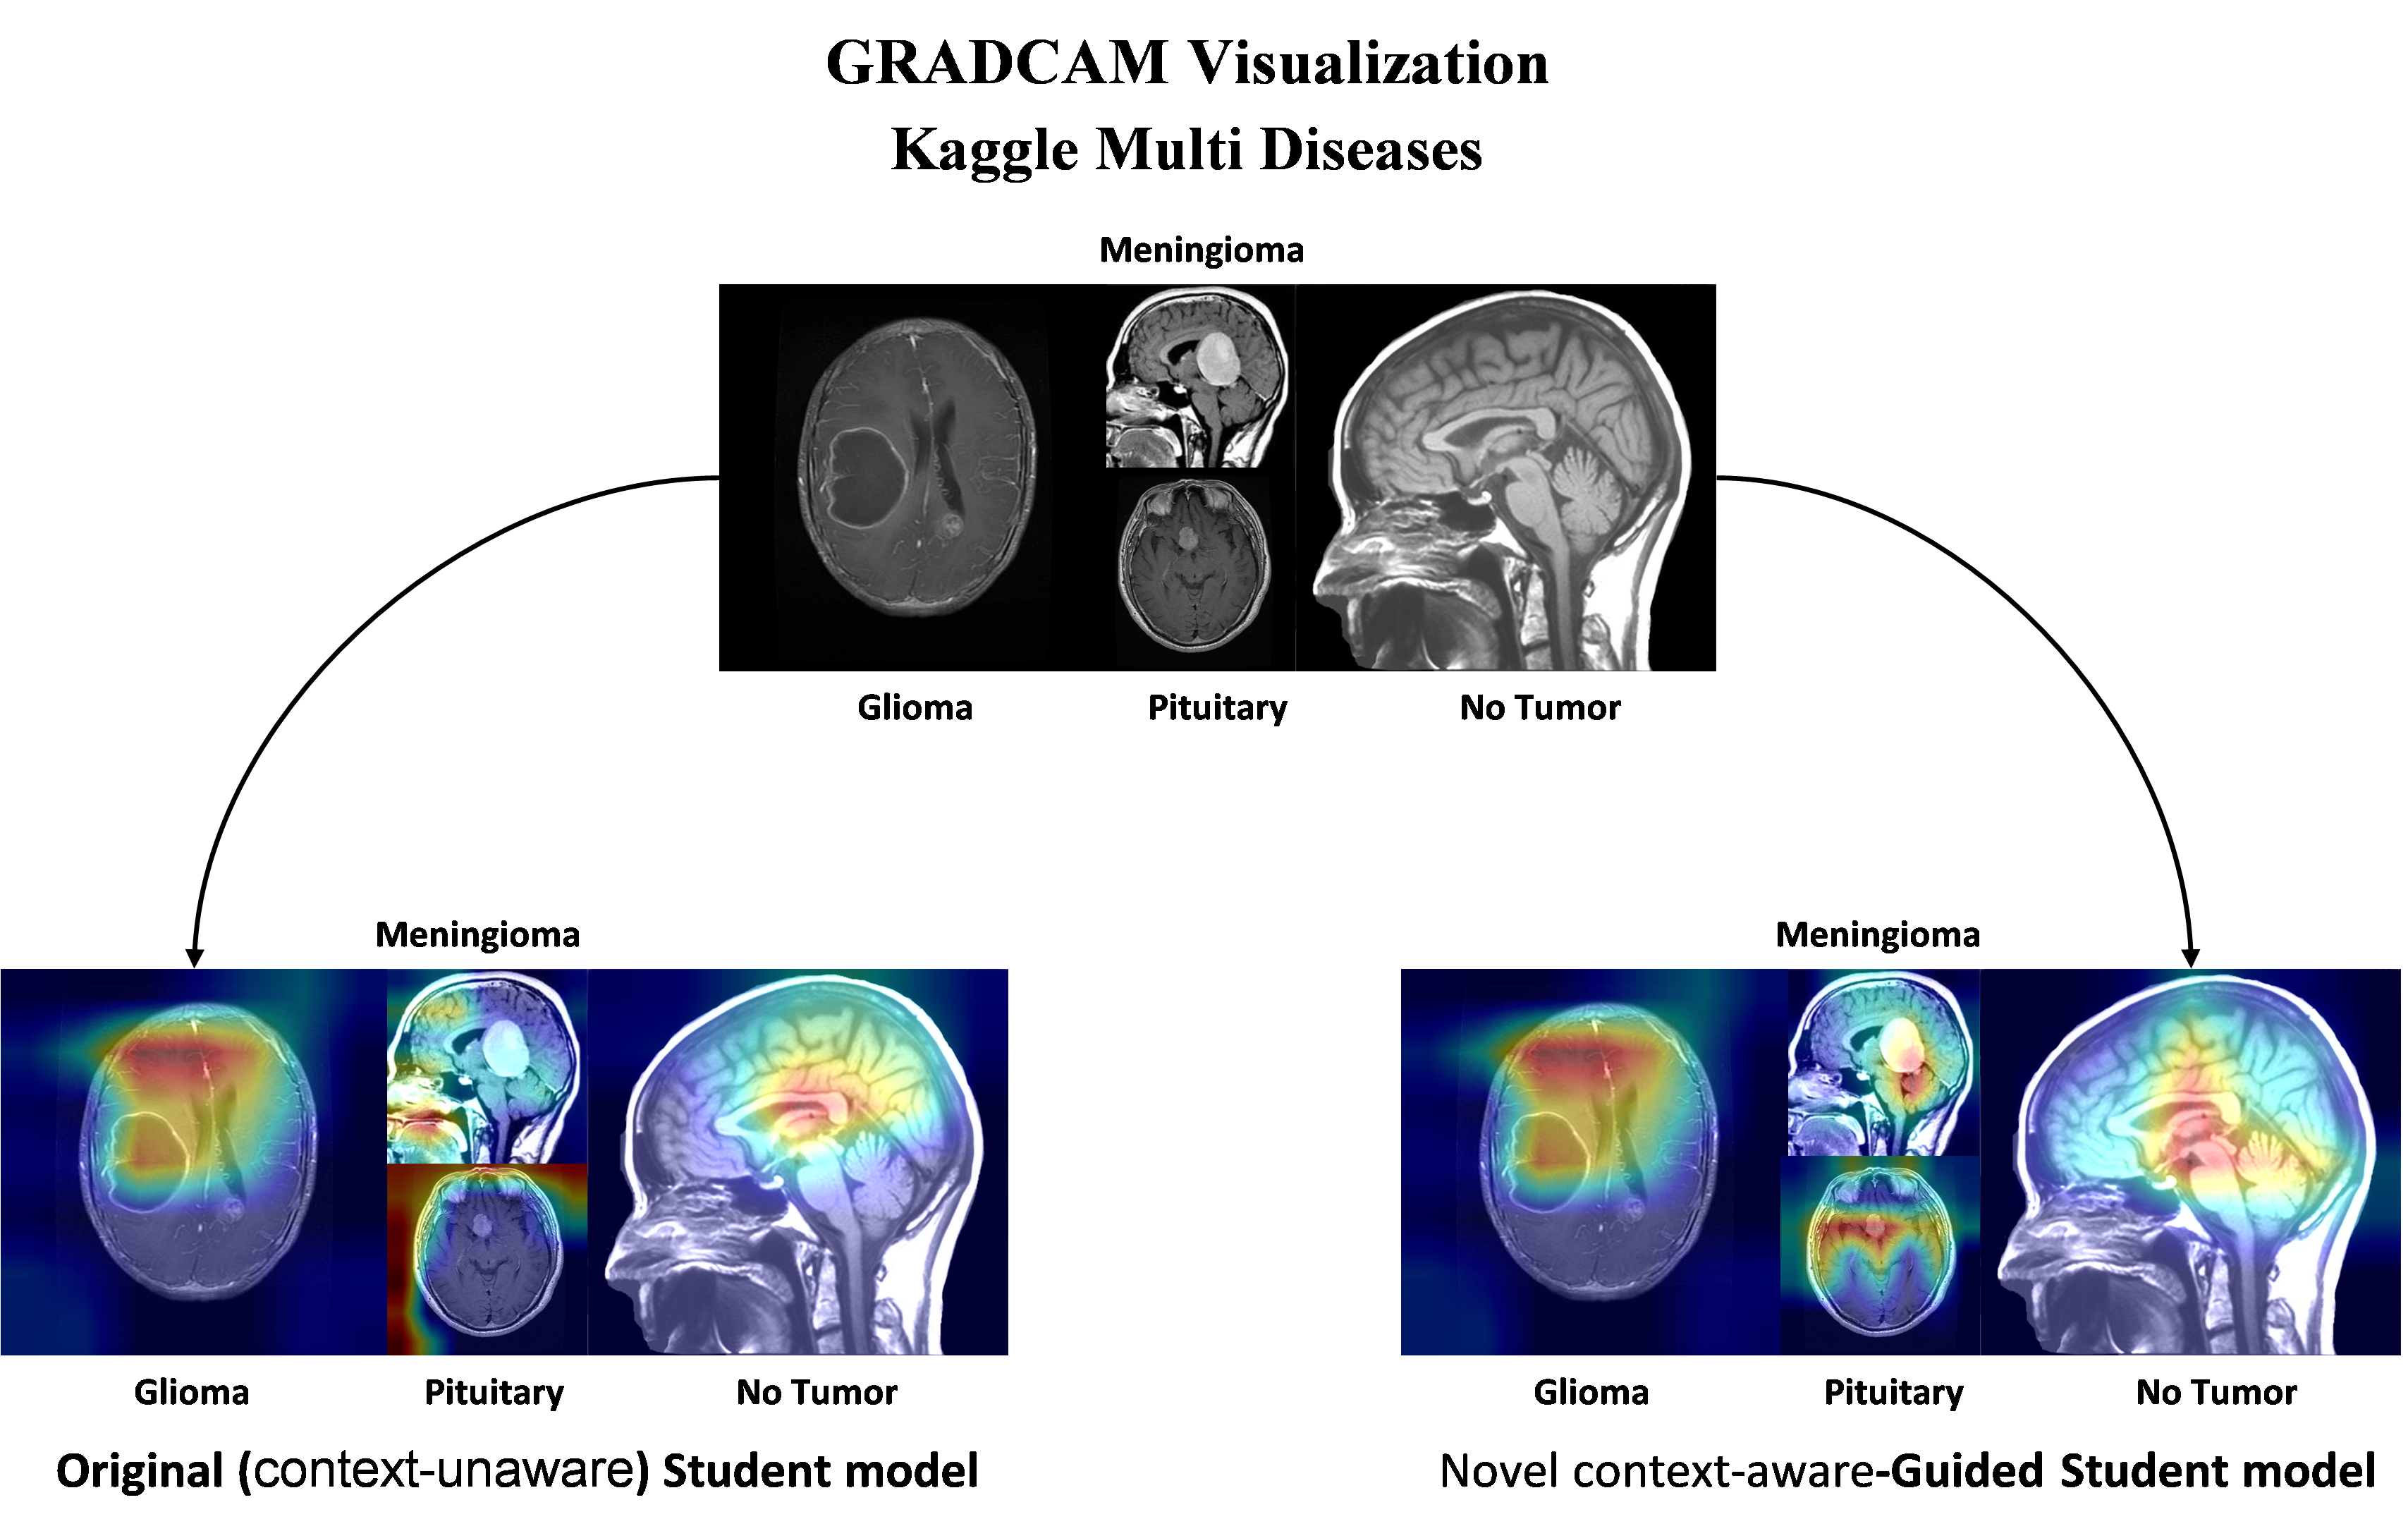

4.6 Interpretability analysis of Context-aware Student model

GRADCAM has used to enhance the interpretability of the Context-aware student model by visualizing which parts of the image influence the model predictions. This is crucial in medical image analysis, especially for tasks like brain tumor detection, where understanding the model decision-making process is essential. GRADCAM helps highlight important image areas, showing how context-aware Guided adjustments to the temperature parameter impact the student model learning, thus improving transparency in the model predictions.

4.6.1 GRADCAM visualization

GRADCAM (Gradient-weighted Class Activation Mapping) [19] is employed to visualize the regions of interest that the Context-aware Student model focuses on when making its predictions. This technique serves to bridge the gap between model performance and human interpretability by enabling us to understand the specific areas in the input images that influence the decisions of the model. By computing gradients of the target class with respect to the final convolutional layer, GRADCAM highlights the salient features in the input image that contribute most significantly to the classification outcome. This visualization aids in identifying if the model is focusing on relevant regions pertinent to tumor detection, thereby providing insights into its reliability and dependability. By applying GRAD-CAM as a visualization technique, we are not only able to validate the predictions of the model but also enhance its confidence in application for clinical tasks. Fig 11 presents the Kaggle multiclass dataset GRADCAM visualization.

Refer to caption

Figure 11: Kaggle Multiclass Dataset GRADCAM Visualization